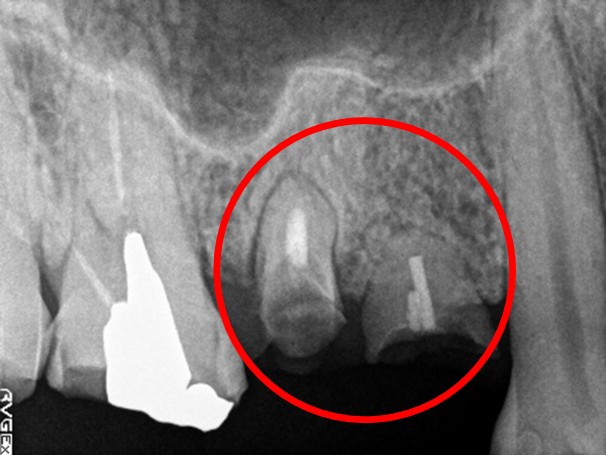

レントゲンで詳しく診てみると、虫歯が歯根のほうまで進行し、保存することができないことがわかり、抜歯しました。抜歯後、骨が大きく欠損していましたので、骨造成を行いインプラントを2本埋入しました。

所感

抜歯後の欠損したところを補う方法には、部分入れ歯、ブリッジ、インプラントがあることを説明したところ、自分の歯と同じような感覚で嚙むことができるインプラントを選択されました。この方は、2016年に右下にインプラント治療をし、インプラントの良さを十分に理解しておられましたので、今回も2本歯を失ったところにインプラント治療を希望されました。今回もX-Guideを使った埋入で、安心安全に行うことできました。

Before

【抜歯後】

After